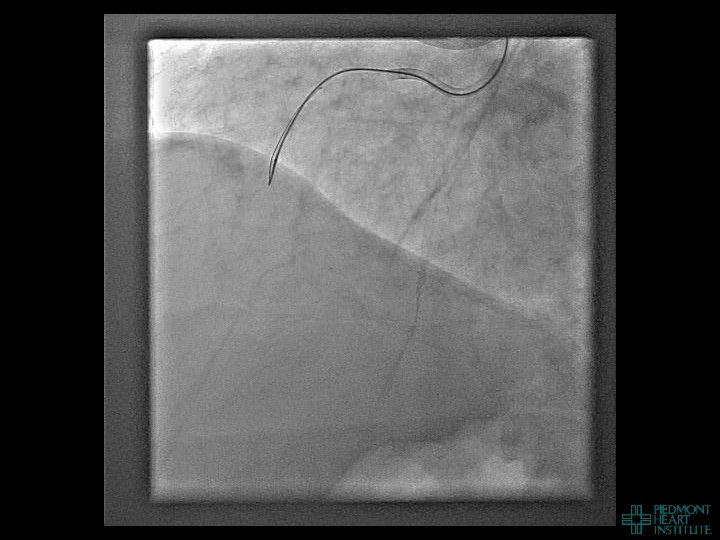

Case Example 4